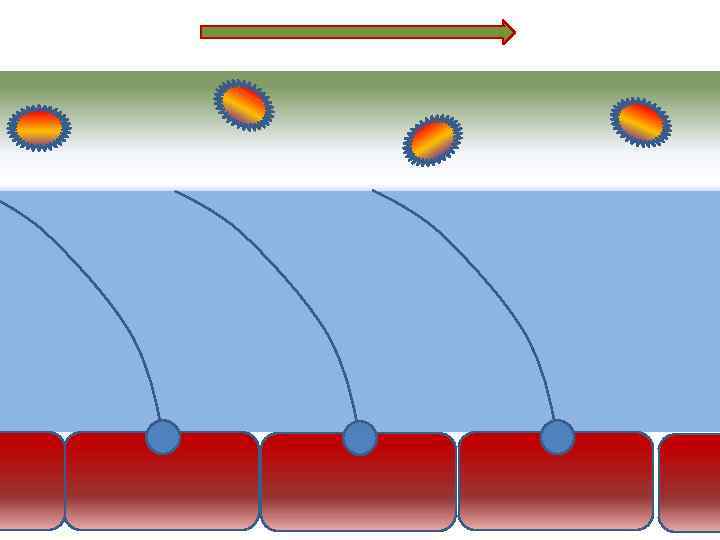

Движение клеток реснитчатого эпителия Движение вперед 1 – 3 Обратное движение 4 – 8

Движение клеток реснитчатого эпителия Движение вперед 1 – 3 Обратное движение 4 – 8

Оптимальное увлажнение Достаточная продукция слизи Хороший транспорт Экономит энергию и воду Защитная функция

Оптимальное увлажнение Достаточная продукция слизи Хороший транспорт Экономит энергию и воду Защитная функция

Механизм защиты легкого Слизь (зеленый цвет) нейтрализует и связывает патогенную флору(синий цвет) Слизь – это барьер между клетками и патогенной флорой Слизь – это транспортное средство

Механизм защиты легкого Слизь (зеленый цвет) нейтрализует и связывает патогенную флору(синий цвет) Слизь – это барьер между клетками и патогенной флорой Слизь – это транспортное средство

Нормальное состояние слизистого бронхиального секрета возможно только при 100% относительной влажности воздуха

Нормальное состояние слизистого бронхиального секрета возможно только при 100% относительной влажности воздуха

Плохое увлажнение • Вязкая слизь - потеря ресничек • Высушивание слизистой смерть клеток • Высушивание слизи в бронхиолах-ателектазы • Затраты энергии на согревание воздуха • Затраты воды на увлажнение

Плохое увлажнение • Вязкая слизь - потеря ресничек • Высушивание слизистой смерть клеток • Высушивание слизи в бронхиолах-ателектазы • Затраты энергии на согревание воздуха • Затраты воды на увлажнение